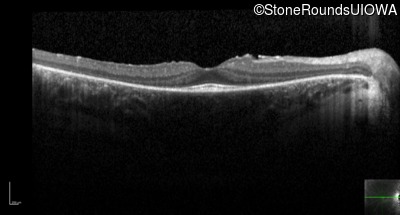

Optical Coherence Tomography - Right - 20/20 -2

Exemplar / OCT Stack